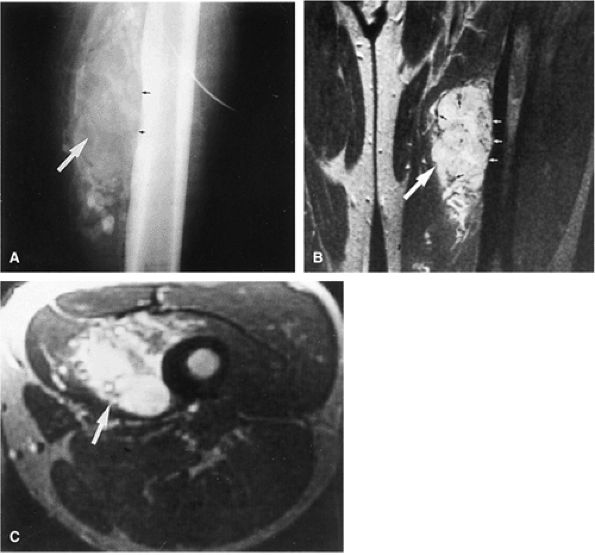

![]() |

FIGURE 14-2 ● Osteosarcoma of the distal tibia is seen on a sagittal proton density-weighted image. Cortical thinning and periosteal reaction are demonstrated (arrow).

FIGURE 14-3 ● Chondrosarcoma of the proximal femoral shaft is seen on a coronal T1-weighted image. Cortical thickening (arrow) demonstrates low signal intensity on the T1-weighted image.

FIGURE 14-4 ● Sagittal fat-suppressed T2-weighted fast spin-echo image demonstrates chondrosarcoma of the humeral shaft. Histologically confirmed hyperintense subcortical tumor infiltration (arrow) is identified.